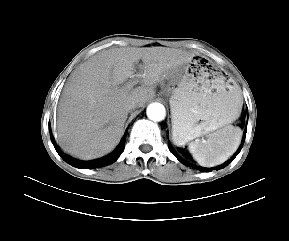

标题: CT19533:病变来源于哪?

患者,男,发现上腹部包块两月余。

病变位于肝胃间隙,实际就是位于小网膜囊(左肝下后间隙),呈轻度不均匀性强化,腹腔内及腹膜后见多发肿大淋巴结。所以我考虑肝胃间隙恶性胃肠间质瘤并淋巴结转移。

病灶强化不显著,灶周及腹膜后见多量淋巴结肿大,考虑淋巴瘤可能,其次考虑间质瘤

病灶与胰腺分界不清,来源于胰腺?

强化后病变与胃壁分界清楚,并且血供不是来源胃壁血管。考虑胰腺颈体癌并腹腔腹膜后淋巴结转移。